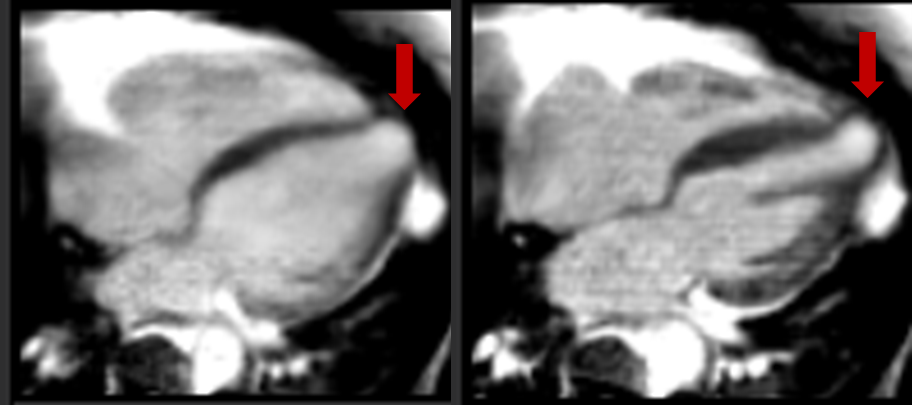

Figure 2. On the top row, lateral wall LGE can be seen, confirmed with a dark blood acquisition. On the bottom row, the enhanced apical aneurysm is apparent (red arrows).